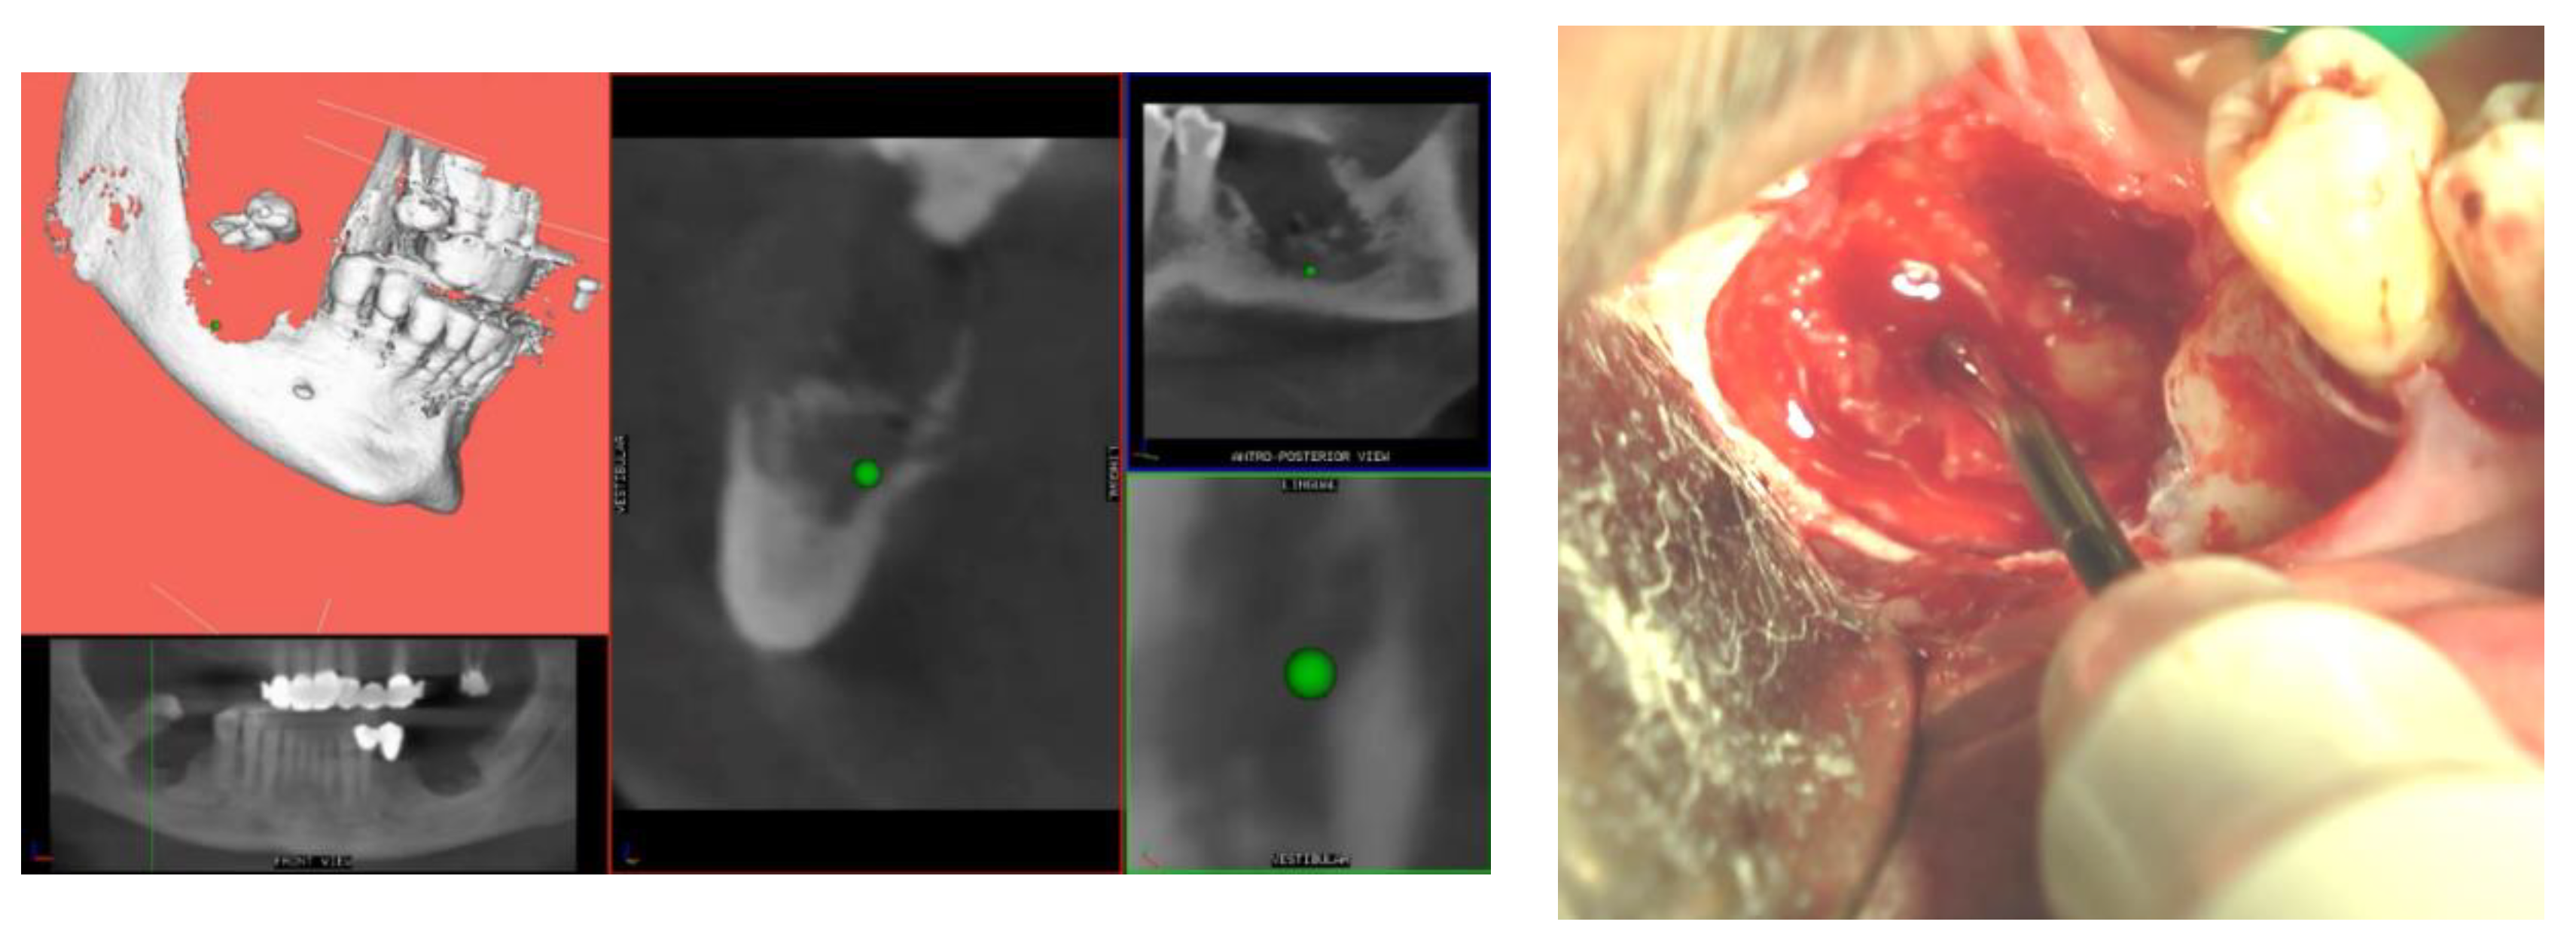

- Pre-operative evaluation. The patient undergoes a cone-beam CT exam with a reference plate containing the fiducial markers, fixed on his inferior teeth. The Digital Imaging and Communications in Medicine (DICOM) were imported into the navigation software.

- Just before surgery, the patient wears the reference plate with the patient reference tool attached onto it and the handle reference tool on the piezoelectric handpiece. The calibration of the navigator system, accomplished in this phase, is performed through a connection reproducing the universal joint for the drills embedded into the calibration tool, allowing the navigation system software to identify the drill position and axis in relation to the patient position and to the CT imaging data.

- Surgery timing. The surgeon can follow in real time the ultrasonic tip position onto the system screen displaying the CBCT images and safely identify and remove the necrotic bone surrounding the inferior alveolar nerve on the right side.